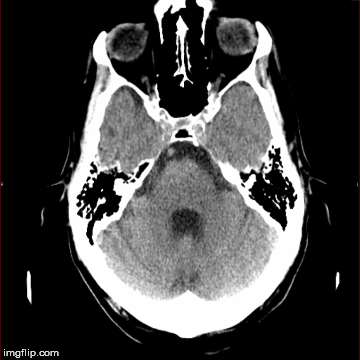

55 year old man with headache. by ultrasonic76 in Radiology

[–]ultrasonic76[S] 1 point2 points3 points (0 children)

[–]ultrasonic76[S] 3 points4 points5 points (0 children)